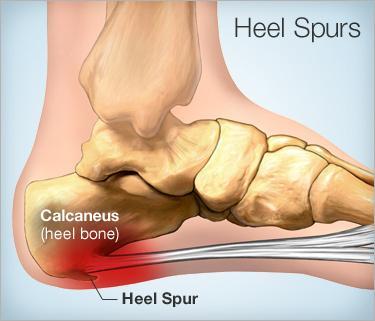

Diese schmerzlindernden Unterstützungssocken mit 7 Lagen sind optimal für Personen, die an Fersenschmerzen leiden, insbesondere wenn sie chronisch sind, sowie bei Plantarfasziitis, Achillessehnenentzündung, Plattfüßen, diabetischen Fußproblemen oder einfach bei müden und überlasteten Füßen.

SCHMERZLINDUNG: Egal, ob Sie zum Fitnesscenter sprinten, zur Arbeit gehen oder sich morgens aus dem Bett erheben, unsere Füße sind unerlässlich! Aber stechende, schmerzende Beschwerden im Fußgewölbe, in der Ferse oder im Knöchel können Sie aufhalten! Kehren Sie zurück zu einer großartigen Fußgesundheit! Das Tragen eines Paares unserer Socken kann Fußgewölbeschmerzen lindern und die Blutzirkulation ankurbeln, was Erleichterung bei Beschwerden wie morgendlichen Fußschmerzen, Plantarfasziitis und Blutansammlungen bringt.

- Bekämpft Symptome der Plantarfasziitis